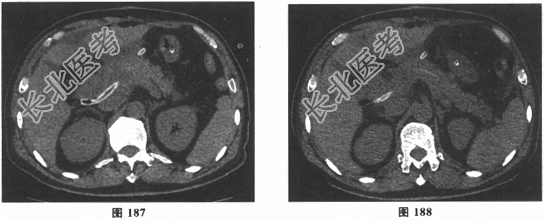

- 多项选择题8.术后第10天(POD10)患者出现腹痛伴腹胀,体温最高38.6℃, 无寒战。查体:P102次/分、R18次/分、BP111/77mmHg, 腹部稍膨隆,全腹有压痛, 轻反跳痛,移动性浊音阴性, 肠鸣音弱。复查腹部CT见图187、图188。给予胰肠后引流管负压吸引2小时,无明显液体引出, 后改为被动引流。腹痛症状逐渐缓解。术后第12天夜间出现胰肠前、脾窝引流液混有少量血性渗液,未予特殊处理后好转。第13天晨查房时发现为少量陈旧性血性渗液。请问该患者目前最应迫切采取的措施是( )